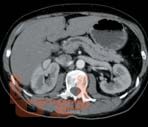

В руководстве приведен анализ и систематизирован опыт Института хирургии им. А.В. Вишневского и зарубежных авторов по вопросам диагностики и хирургического лечения кистозных опухолей поджелудочной железы. Описаны клинические проявления и анамнестические данные, характерные для таких пациентов. Дана ультразвуковая, компьютерно-томографическая, магнитно-резонансно-томографическая и эндоультразвуковая семиотика кистозных опухолей. Показаны возможности пункционной диагностики с исследованием цитологического состава кистозных опухолей и определением уровня онкомаркеров в их содержимом.